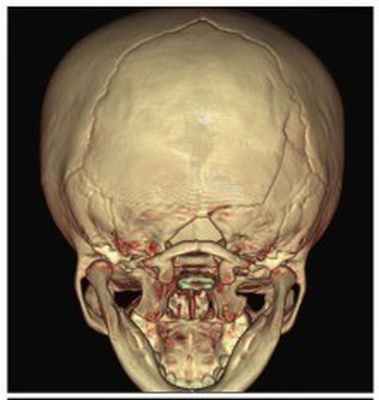

а) Сагиттальный краниосиностоз. Частота сагиттального синостоза по результатам нескольких крупных исследований составила 30-50% (Hunter и Rudd, 1976; Lajeunie et al., 1996; Singer et al., 1999). У мальчиков заболевание встречается гораздо чаще, чем у девочек. Отмечается характерный внешний вид головы с длинным узким черепом и нормальным строением лица. Костный выступ пальпируется в области сагиттального шва. Окружность головы обычно превышает средний нормальный для данного возраста размер на 2-3 стандартных отклонения. Деформация выявляется при рождении, а также видна на рентгенограмме плода (личные наблюдения).

Скафоцефалия вследствие преждевременного сращения сагиттального шва: длинный узкий череп.